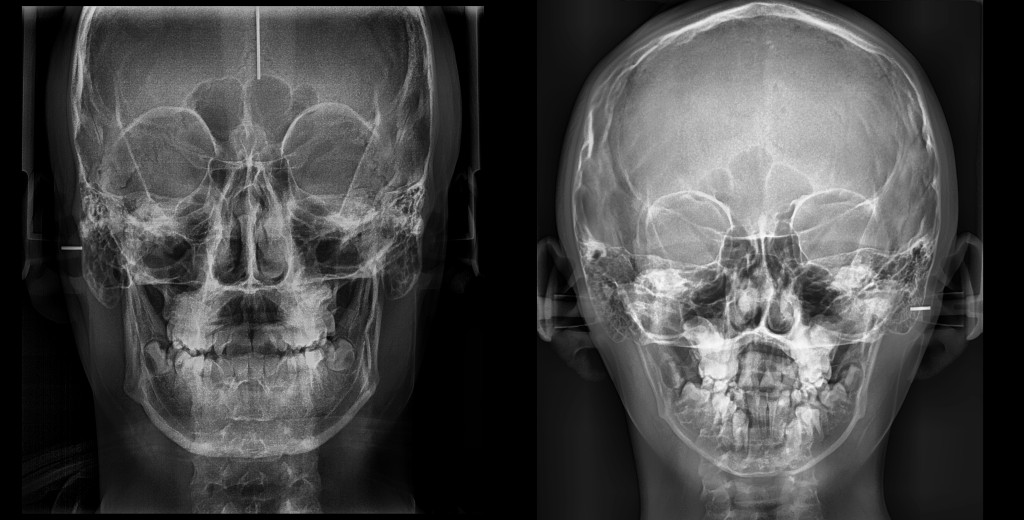

CEFALOMETRÍA AP

Ver de frente, no es solo un ángulo. Es una forma de entender la historia completa del paciente.

Diagnóstico de Asimetrías Esqueléticas y Dentales, Planificación Quirúrgica y Ortodóncica, Planificación de Expansiones Maxilares.